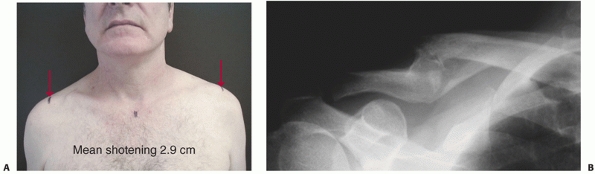

Clinically, a visibly deformed shoulder on inspection usually corresponds to a minimum of 2 cm of shortening radiographically (Fig. 36-24).

FIGURE 36-24

The typical clinical deformity following a displaced left midshaft clavicular fracture with a short, droopy, “ptotic” shoulder with anterior translation and rotation of the distal fragment and limb.  |